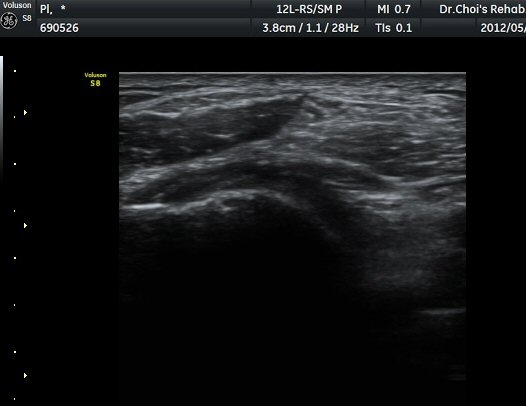

À­´Ù¸®(thigh) ¾Æ·¡ ºÎÀ§ ¿ÜÃø Ⱦ´Ü¸é°Ë»ç¿¡¼­ À̵ιڱ٠³»Ãø¿¡¼­ ÃѺñ°ñ½Å°æÀÌ Á¤»óÀûÀ¸·Î °üÂûµÈ´Ù(±×¸² 1, 2).

ŽÃËÀÚ¸¦ ¾Æ·¡·Î À̵¿ÇÏ¿© ºñ°ñµÎ ºÎÀ§±îÁö ÃѺñ°ñ½Å°æÀÇ ÁÖÇàÀ» µû¶ó ½Å°æÀ» È®ÀÎÇÏ¿´´Ù(±×¸² 3, 4).

ŽÃËÁö¸¦ Á¶±Ý ´õ ¾Æ·¡·Î À̵¿ÇÏ´Ï »ÀÀÇ µÎ²²°¡ °¨¼ÒÇÏ´Â °ÍÀ» º¸°í ºñ°ñÀÇ ¸ñ ºÎÀ§¸¦ °üÂûÇϰí ÀÖÀ½À» ¾Ë ¼ö ÀÖ°í ÃѺñ°ñ ½Å°æÀº ºñ°ñ ¸ñ Ç¥Ãþ¿¡¼­ °üÂûµÈ´Ù(±×¸² 5).

ŽÃËÀÚ¸¦ Á¶±Ý ´õ ¾Æ·¡·Î À̵¿ÇÏ´Ï ºñ°ñÀÇ ¾ÕÂÊ¿¡¼­ ÃѺñ°ñ½Å°æ õºñ°ñ½Å°æ°ú ½Éºñ°ñ½Å°æÀ¸·Î ³ª´©¾îÁø´Ù(±×¸² 6).

ŽÃËÀÚ¸¦ ´õ ¾Æ·¡·Î À̵¿ÇÏ´Ï Ãµºñ°ñ½Å°æÀÌ Àú¿¡ÄÚ µÕ±Ù µ¢¾î¸®·Î °üÂûµÇ´Ù°¡ ´Ù½Ã Á¤»óÀûÀÎ ¸ð½ÀÀ¸·Î °üÂûµÈ´Ù(±×¸² 7, 8).